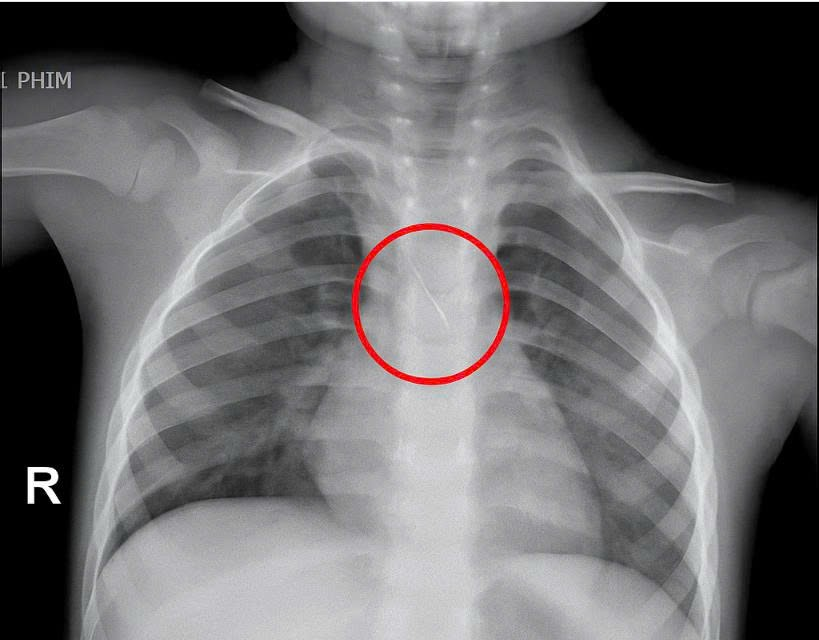

Trước đó, bé nhập viện trong tình trạng ho nhiều, ho sặc. Qua thăm khám và chụp phim, các bác sĩ xác định bé bị sặc kim chọc tủy dài khoảng 22mm, vị trí mắc tại góc carina, nơi chia đôi khí quản. Đây được đánh giá là ca cấp cứu nguy hiểm.

Bệnh viện kích hoạt hội chẩn liên khoa và quyết định tiến hành nội soi phế quản cấp cứu. Dị vật được phát hiện với một đầu nhọn cắm vào đoạn dưới khí quản, đầu còn lại nằm trong phế quản gốc trái.